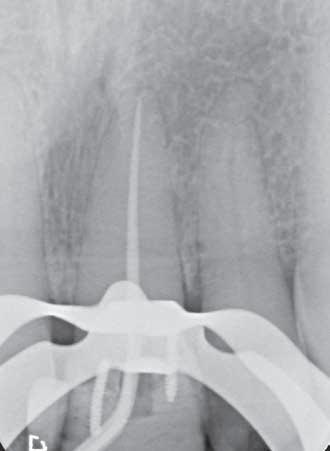

The HyFlex OGSF sequence from COLTENE was the system of choice for this procedure, due to the system’s excellent cutting efficiency. All of the files in the sequence, consisting of an Orifice Opener, Glidepath File, Shaping File and Finishing File were employed, with irrigation between each file. Locating the canal was challenging due to the extent of the calcification. Establishing the location took time, and required a dental microscope. Once the tooth was opened with the Orifice Opener, it was over to a MicroMega K-File ISO 08 to reach as deep down as possible into the canal. Then it was the turn of the Glidepath File, 1mm short of the length achieved with the K-File, and this process was repeated all the way to the root apex.

Once the root was open, the Shaping

File was utilised, ending with the 30/.04 Finishing File to clean out the canal, completing the OGSF sequence. The canal was irrigated using COLTENE CanalProTM NaOCI 3% during the instrumentation and COLTENE CanalProTM EDTA as a finial irrigation. The tooth was restored using a glass ionomer cement, and the patient went back to the dentist for the final restoration.

3: Periapical X-ray to check orientation of file